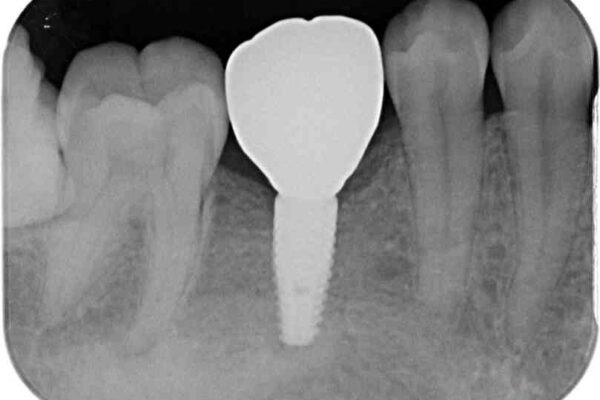

• 空いている時間を利用して通院 奥歯のインプラント治療 治療途中画像